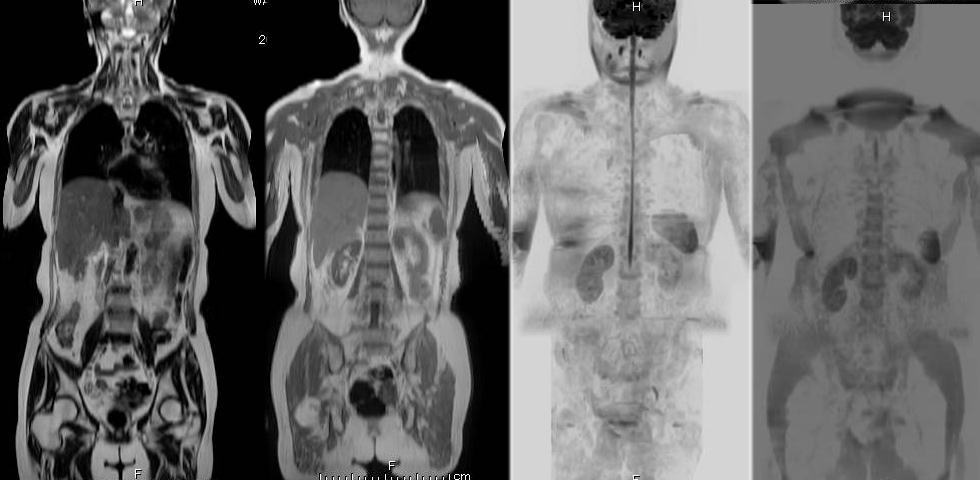

近年、人間ドックではDWIBS(ドゥイブス)と呼ばれるMRI検査が注目されています。DWIBSは「Diffusion Weighted Whole Body Imaging with Background Suppression」の略で、全身のがんを調べることができるMRI検査の一つです。体への負担が少なく、短時間で全身をチェックできることから、人間ドックの新しい検査方法として広がっています。

DWIBSは、MRIの拡散強調画像という技術を利用して、がん細胞の特徴を画像として捉える検査です。がん細胞は正常な細胞に比べて水分子の動きが制限される性質があるため、その違いを利用して異常の可能性を見つけます。

がんは早期に発見することで治療の選択肢が広がります。DWIBSは、症状が現れる前の異常を見つけるための検査として、人間ドックの新しい選択肢となっています。自分の健康状態を知るために、定期的な検査を検討してみてはいかがでしょうか。